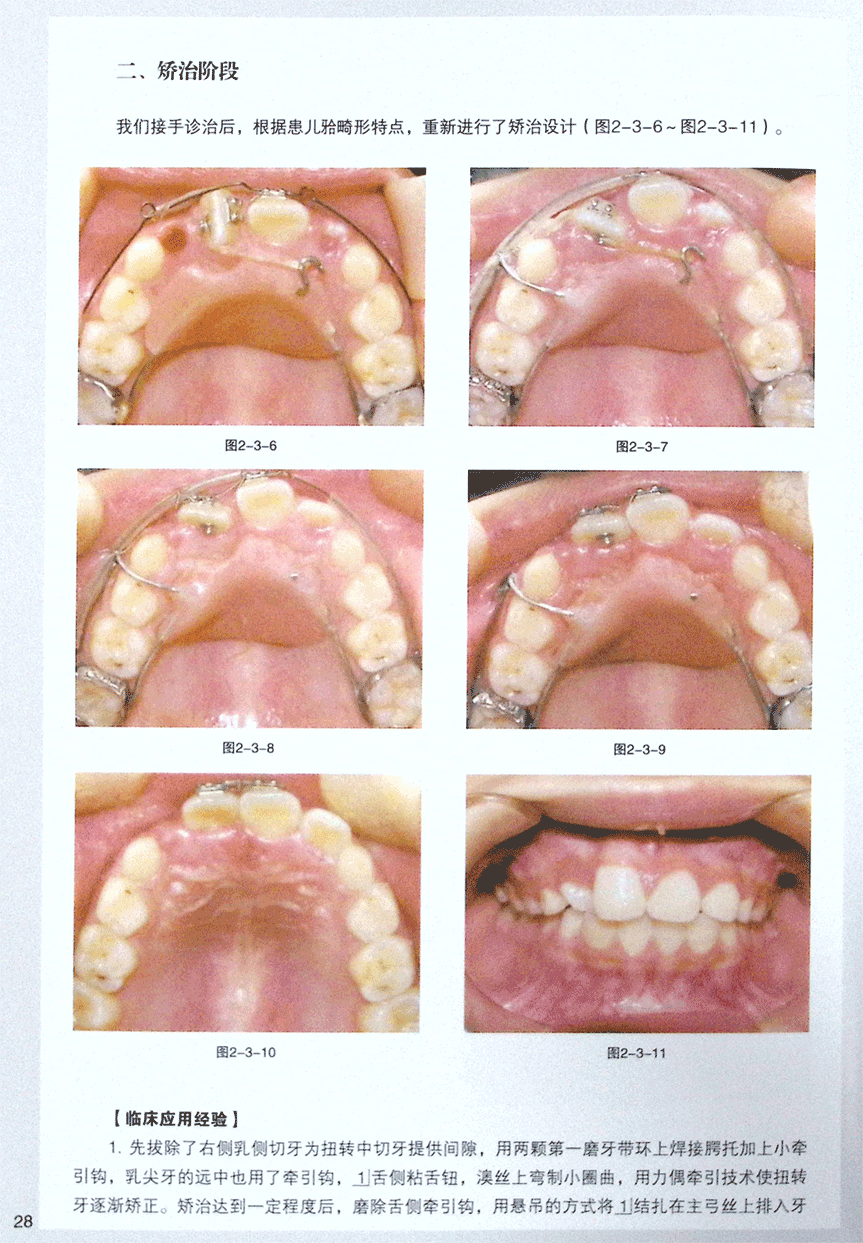

第三节 附牵引钩改良Nance托装置矫治中切牙